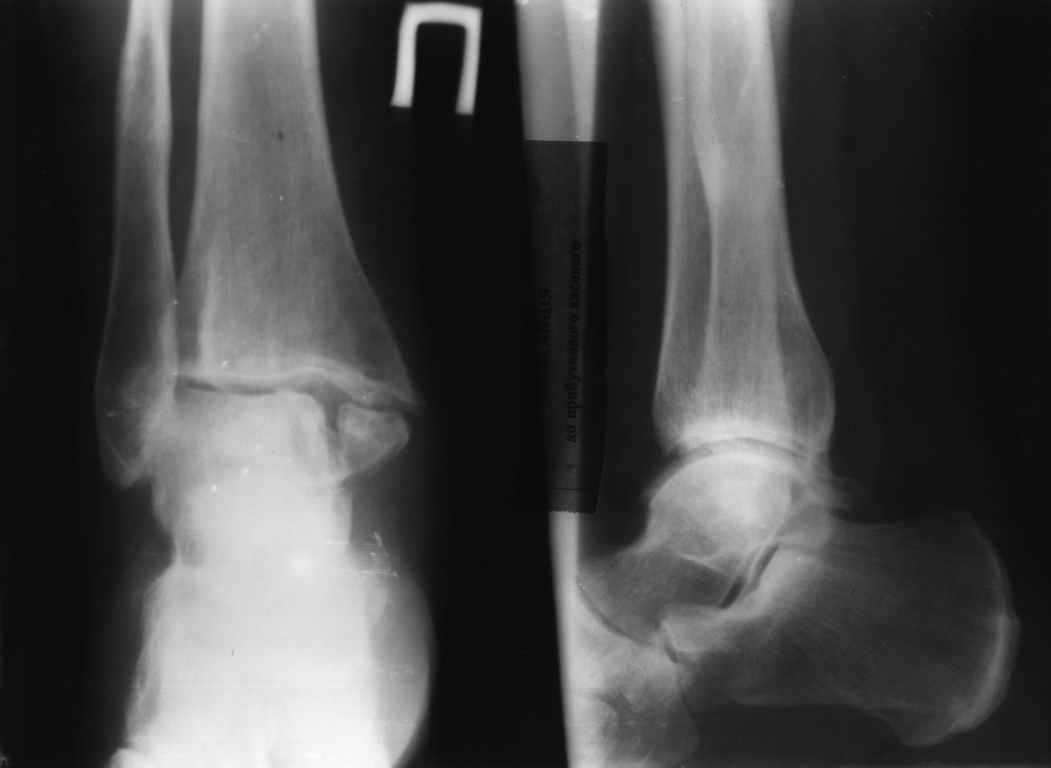

Ложный сустав медиальной лодыжки

Обратилась женщина, 45 лет. Травма 5 лет назад - перелом обеих лодыжек, разрыв синдесмоза. Лечение консервативное

Ув. коллеги, каково Ваше мнение по поводу дальнейшей лечебной тактики.

Явления артроза налицо. Будет ли толк от остеосинтеза лодыжки, болта-стяжки на застарелое повреждение синдезмоза? Или все-таки необходимо ставить вопрос об артродезировании (расходы на эндопротезирование не сможет оплатить)